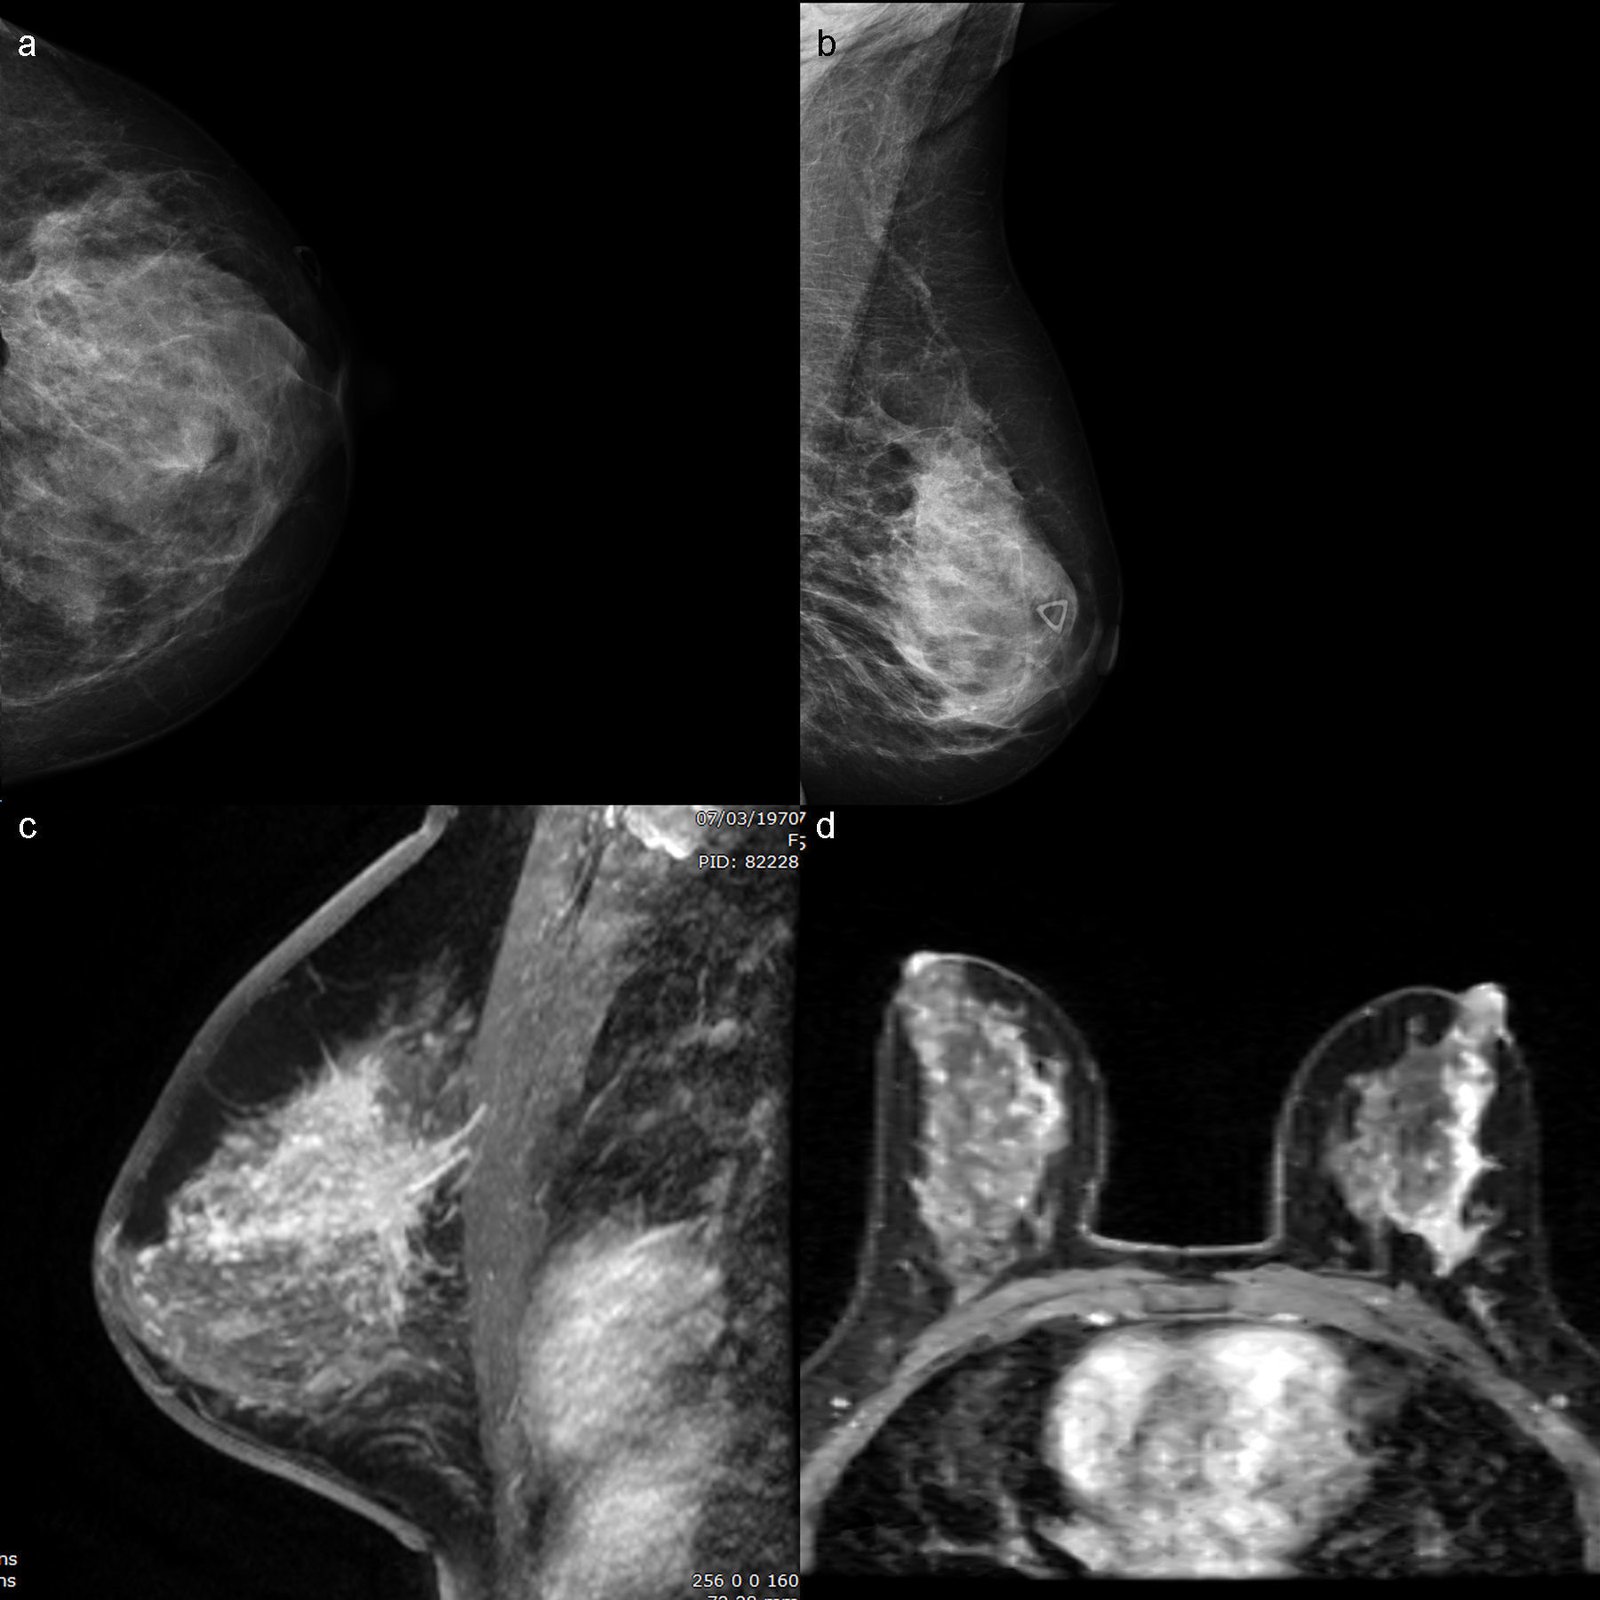

Diagnóstico especializado en salud de la mujer

Ofrecemos estudios dirigidos a la detección temprana y evaluación integral de patologías mamarias y ginecológicas, con un enfoque preventivo y diagnóstico de alta precisión.

Resonancia Magnética de Mamas

Evaluación avanzada para detección y caracterización de lesiones.